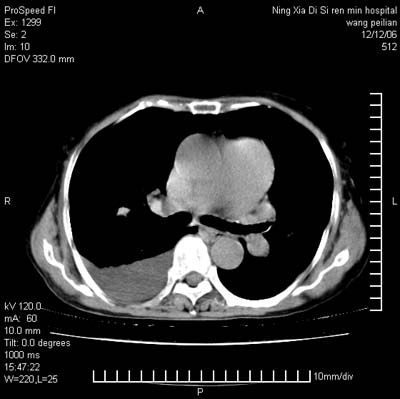

标题: CT5609:胸部:女77 病史不详

两肺可见多个大小不等的结节,左侧有胸水,纵隔淋巴结增大,考虑是细支气管肺泡癌

两肺尖纤维索状影,两下肺结节块状影,且有钙化灶,右胸腔积液。考虑肺结核并胸膜炎。

两肺尖纤维索状影,两下肺结节块状影,且有钙化灶,右胸腔积液。考虑肺结核并胸膜炎肺间质纤维化

考虑:1、慢性支气管炎合并全小叶型肺气肿、间质纤维化;

2、双肺结核;

3、右侧胸膜炎(积液)。

1、双肺继发型肺结核(以纤维、增殖灶为主);

2、右侧胸腔积液;

3、其余符合老年肺改变。

双肺见多个结节状及条索状影,双侧胸腔积液,右侧叶间积液,考虑结核性胸膜炎